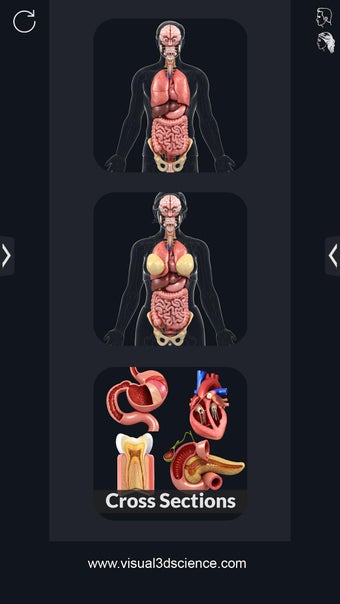

My Organs Anatomy es una aplicación de anatomía 3D gratuita desarrollada por Visual 3D Science para usuarios de Android. Esta aplicación proporciona un modelo 3D altamente realista de los órganos humanos que se puede girar 360°, acercar y alejar, y ver desde cualquier ángulo. La aplicación está diseñada para proporcionar una mirada detallada a la anatomía de los órganos humanos y ofrece varias características para ayudar a los usuarios a explorar y aprender.

La interfaz fácil de usar de My Organs Anatomy permite una navegación sencilla, lo que facilita la selección, rayos X, ocultación y visualización de órganos individuales. La aplicación también incluye un modo de animación, opciones de búsqueda y un panel de información que proporciona información relacionada. Además, la aplicación ofrece pronunciación de audio para todos los términos anatómicos, e incluso los usuarios pueden dibujar o escribir en la pantalla y compartir capturas de pantalla.